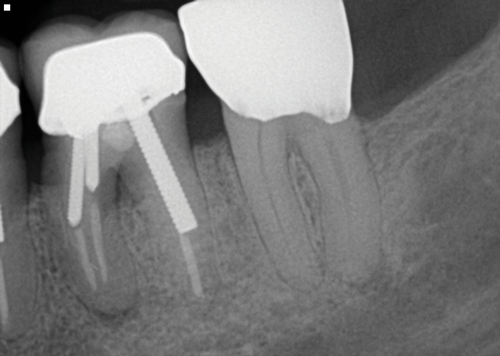

Other common risks associated with post placement include the occurrence of root fracture, perforation, and apical leakage as well as the development of caries (Figure 1 through Figure 3).9 How the post space is prepared significantly affects the ability of the root canal filling material to create a seal.11 Apical leakage increases in correlation with the amount of gutta percha removed from an endodontically treated tooth, increasing the risk of reinfection.11 The risks of fracture and perforation must also be seriously considered. After the performance of endodontic treatment alone, furcation-side dentin thickness in the distal roots of mandibular molars has been shown to be less than 1 mm in more than 80% of teeth.12 After preparation of the post space, the remaining dentin thickness in the buccal roots of premolars has been shown to be often less than 1 mm.13 The remaining thickness of the root dentin after endodontic and post placement procedures is the factor most highly correlated with future resistance against root fractures.13 These anatomic studies underscore the need for judicious preparation, and the risks of post placement underscore the need for careful case selection.

(1.) A radiograph of a root fracture associated with a threaded post, cone-beam computed tomography views of a perforation associated with a post, and a radiograph demonstrating evidence of apical leakage associated with posts, respectively.

Figure 1

(2.) A radiograph of a root fracture associated with a threaded post, cone-beam computed tomography views of a perforation associated with a post, and a radiograph demonstrating evidence of apical leakage associated with posts, respectively.

Figure 2

(3.) A radiograph of a root fracture associated with a threaded post, cone-beam computed tomography views of a perforation associated with a post, and a radiograph demonstrating evidence of apical leakage associated with posts, respectively.

Figure 3